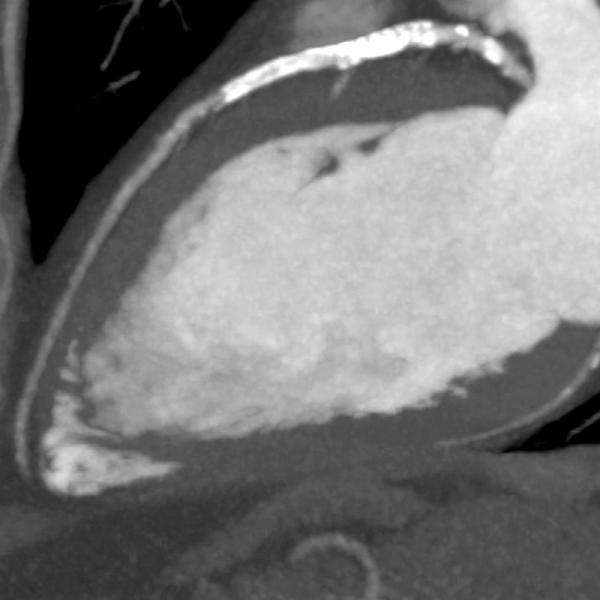

A team of doctors at The Hospital for Sick Children (SickKids) in Ontario, Canada, have, for the first time in North America, successfully destroyed a bone tumor using high-intensity ultrasound guided by magnetic resonance imaging (MRI), rather than traditional surgery.